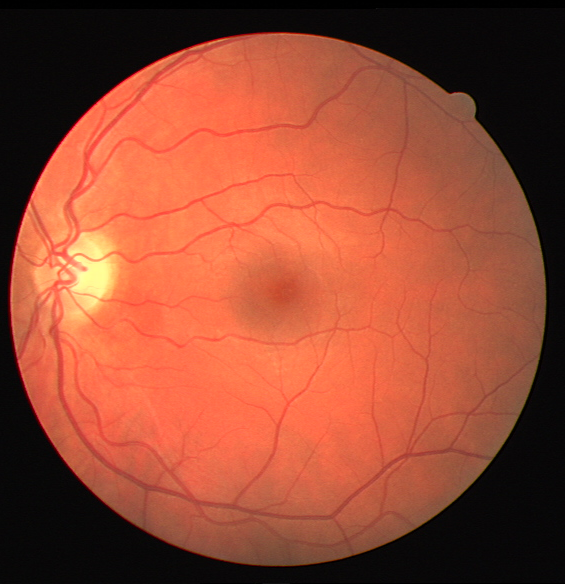

The visual differentiation between arteries and veins can be difficult in some cases, like small vessels with poor contrast and not clearly connected to a specific arterial or venular tree. These cases can be identified with certainty as vessels, but their classification into arteries and veins is uncertain, even for an expert. Additionally, it is common to find crossings between arteries and veins in the retina. Thus, although for these positions either the artery or the vein is above the other, these pixels can be regarded as simultaneously belonging to both types of vessels. This allows to account for continuous arterial and venular trees regardless of crossings below the other one. The identification of these two special situations (uncertain vessels, and vessel crossings) is common in manually annotated retinal vessel classification datasets [38, 42, 43, 44]. Figure 1 shows an example of a ground truth image from the RITE dataset labelled this way, along with its decomposition into arteries, veins, crossings and uncertain vessels.

In Figure 4, an example of a retinography before and after applying the preprocessing method is provided, along with the density histograms of vessel pixels and background pixels for each image. The histograms have been computed from the images converted to grayscale.

Also, an example of a retinography and its corresponding vasculature segmentation and A/V classification ground truths is depicted in Figure 6.